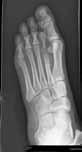

En mamma söker dig med sin 6-årige pojke eftersom hon noterat att pojken är ”plattfot” och önskar hålfotsinlägg. Han är frisk och har inga subjektiva symptom av detta. Mamman är orolig.

Hur undersöker du pojken?

Vad ger du mamman för besked om din undersökning i övrigt är normal?

Vad föreslår du för åtgärd?

Svar: Ledlaxitet?

Knävalgitet?

Neurologi?

Ryggstatus?

Fot-, fotledsstatus? 3p

Lugnande besked. 1p

Det finns inget skäl att ge denne symptomfrie pojke inlägg eller specialskor. Inga studier visar att detta skulle kunna ”bygga” fotvalvet eller förbättra prognosen avseende framtida besvär. 1p